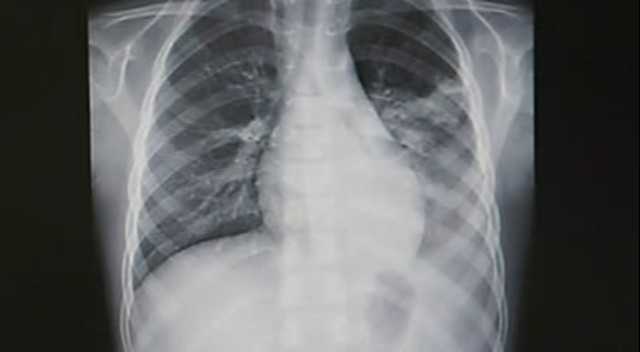

건강검진 때 '흉부 엑스레이' 맨날 찍었는데···이제 50살 이상만 검사, 왜?

정부가 국가건강점진 흉부 방사선(엑스레이) 검사 연령을 20세 이상에서 50세 이상으로 조정하기로 했다.

정부가 국가건강점진 흉부 방사선(엑스레이) 검사 연령을 20세 이상에서 50세 이상으로 조정하기로 했다. 20~49세 고위험 직업군은 검사 대상에 포함해 한시적으로 지원한다. 폐결핵 발견율은 지극히 낮은데 매년 1400억원 넘는 예산이 투입되는 등 효과가 떨어진다는 판단에 따른 조치다.

흉부 방사선 검사는 주로 폐결핵을 발견할 목적으로 시행하나, 폐결핵 유병률은 0.04%에 불과해 주요 국가건강검진 원칙을 미충족하며 검사 효과 대비 비용이 과다하다는 문제가 제기됐다. 2023년 검진 비용은 1426억원으로 전체 검진 비용의 21%에 달한다. 또 검진 이외에 진료를 통한 흉부 방사선 검사 수검 인원도 매년 약 900만명에 달하는 등 중복성 지적도 나왔다.